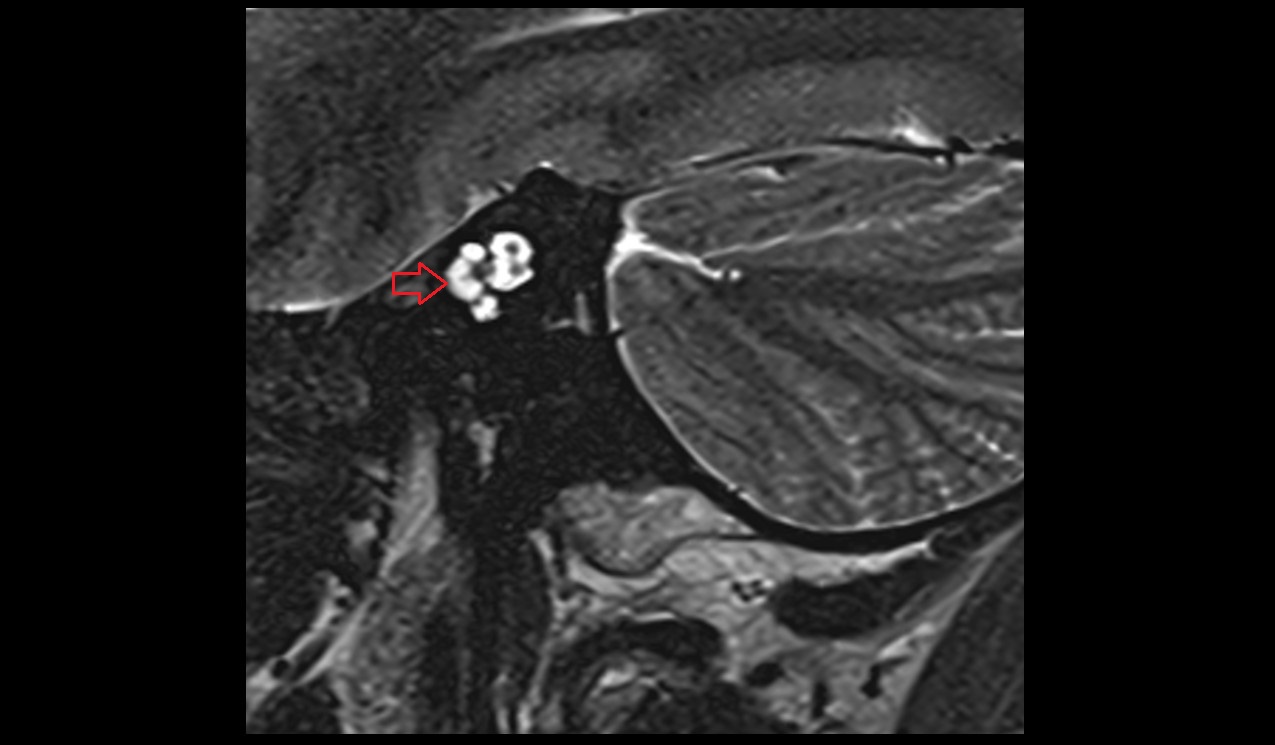

- Articular disc of temporomandibular joint